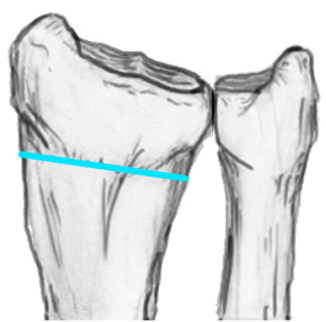

1.  Distal radial Step > 2mm

- leads to RC OA radiographically

- not proven to lead to dysfunction

3.   Radial shortening > 5 mm

- leads to ulnocarpal abutment